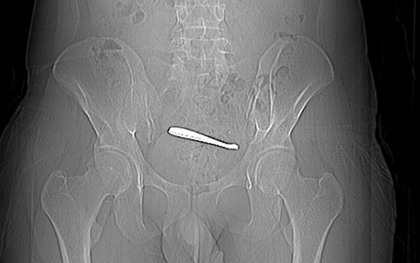

Bệnh nhân 15 tuổi nhập viện vì sốt và đau bụng dữ dội, các bác sĩ đã phẫu thuật cấp cứu thành công, cảnh báo về nguy cơ biến chứng nguy hiểm của ký sinh trùng.